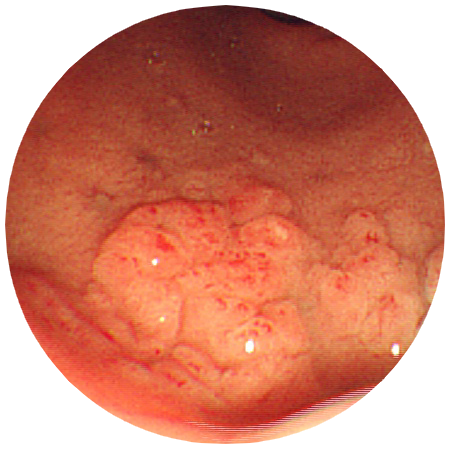

胃疾患

胃アニサキス症

説明